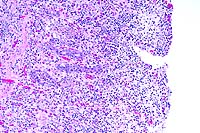

10x

obj

40x

- Case 24-4. Small intestine. Thickened, blunted villi

are expanded by abundant lymphocytes, macrophages, and fewer

eosinophils. The hypertrophic, vacuolated endothelium of a small

arteriole is infiltrated by lymphocytes and neutrophils.